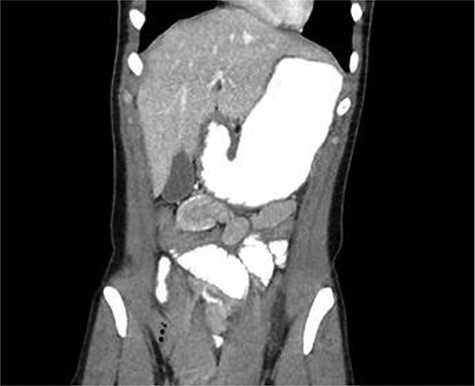

CT scan diagnosed 100% of the cases and all cases were reported as jejunojejunal (JJ) intussusception (Figs 1, 2). CT scan identified two patients having more than one intussuscepted segment. None of the patients were found to have lead points on imaging.

A 24-year-old female with CT scan with target sign in mid-right abdomen suggesting JJ intussusception